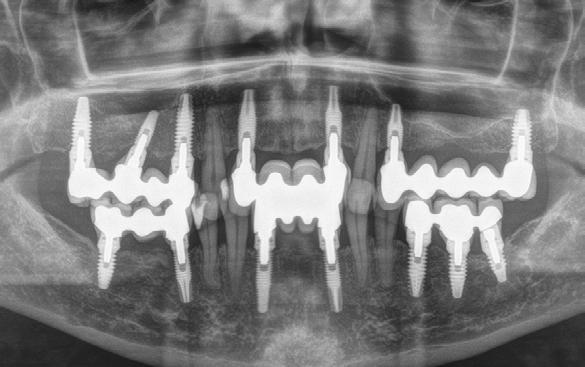

Figura 1. Radiografía panorámica inicial que muestra la enfermedad periodontal avanzada de la paciente, con ausencia de varias piezas dentales y otras de mal pronóstico.

Figura 4. Radiografía tras la primera fasae del tratamiento, con exodoncias realizadas y ferulización de dientes remanentes.

Figura 11. Radiografía a los 8 años de seguimiento, que muestra estabilidad de los tejidos duros con el tratamiento realizado.

Figura 14. Radiografía a los 12 años de seguimiento, con comportamiento estable de dientes e implantes.

Figura 17. Radiografía final que evidencia la estabilidad completa de los tratamientos a los 20 años.